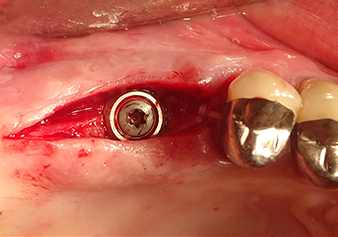

Аугментация внутренних пазух традиционно проводится с помощью мануальных инструментов, использующих ударные движения в сочетании с ротационной подготовкой ложа для имплантата. По мнению специалистов, современные пьезохирургические системы делают эту процедуру значительно менее травматичной; эффект кавитации позволяет использовать их практически без давления. Инструменты используются, с одной стороны, для подготовки ложа имплантата, а с другой - для минимально инвазивного вскрытия дна верхнечелюстной пазухи и гидродинамического поднятия мембраны Шнейдера [8].

В авторской практике мембрана обычно поднимается в два этапа. В качестве альтернативы подходит метод, указанный производителем. В этом случае сначала подготавливается ложе для имплантата, и только затем при помощи инструмента Z35P в небольшом объеме вскрывается костное дно пазухи. В результате очень атравматичного метода пациент не испытывал послеоперационной боли и смог вернуться к работе на следующий день. В практике автора это касается 90% пациентов.